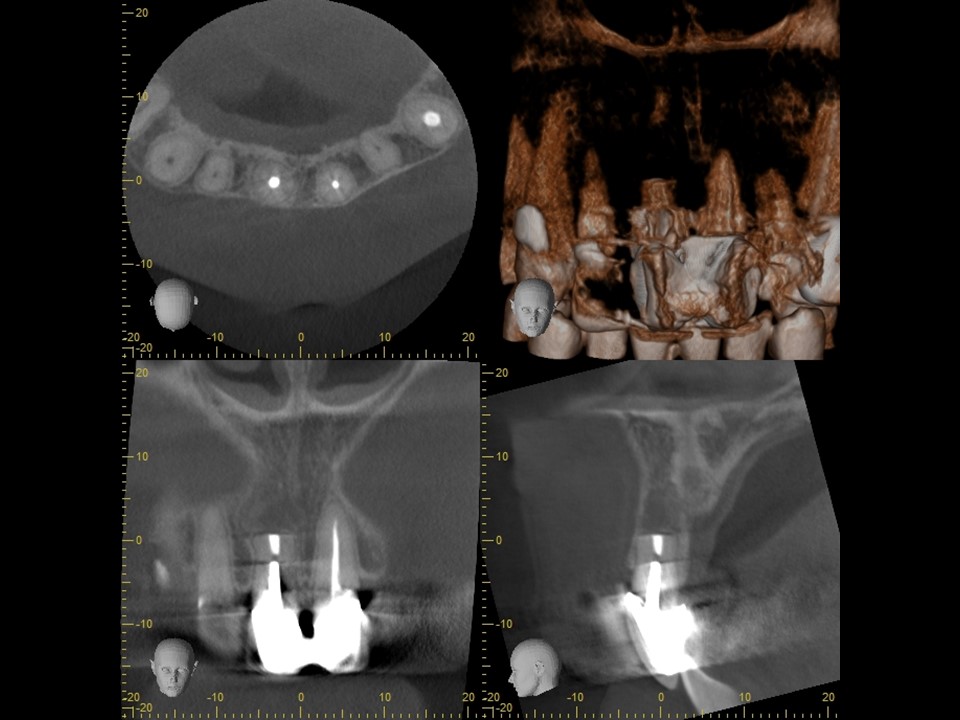

術前レントゲンおよびCT画像です。上顎前歯に連結したセラミッククラウンが装着してありますが、根管充填は不十分です。

根尖部には根尖病変と思われる黒いX線透過像を認めます(矢印)。すでに一度歯根端切除が行われているため、隣在歯と比べて歯根が短くなっています。